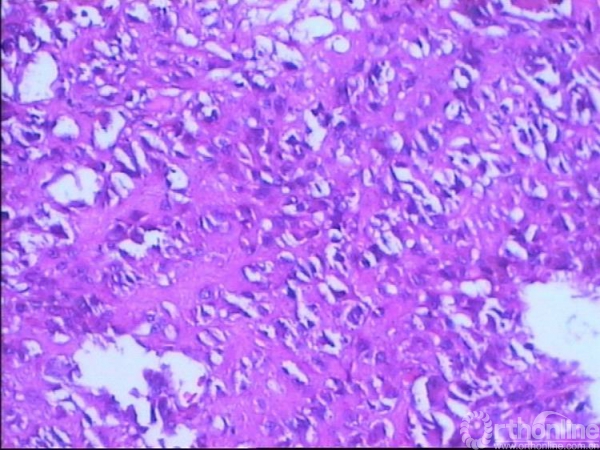

图13-7 病例二术后大体病理镜下表现

高度间变的多角形细胞间骨样组织,片状坏死,符合普通型骨肉瘤。

图13-12 病例一第二次手术术后大体标本冠状剖面表现

图13-13 病例一第二次手术术后大体病理镜下表现